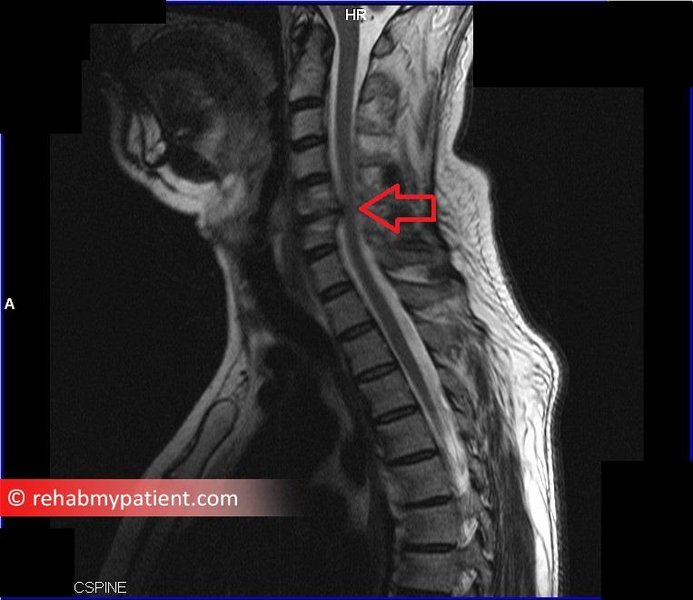

MRI showing cervical radiculopathy

An MRI scan illustrating features consistent with cervical radiculopathy, such as disc herniation or foraminal stenosis.